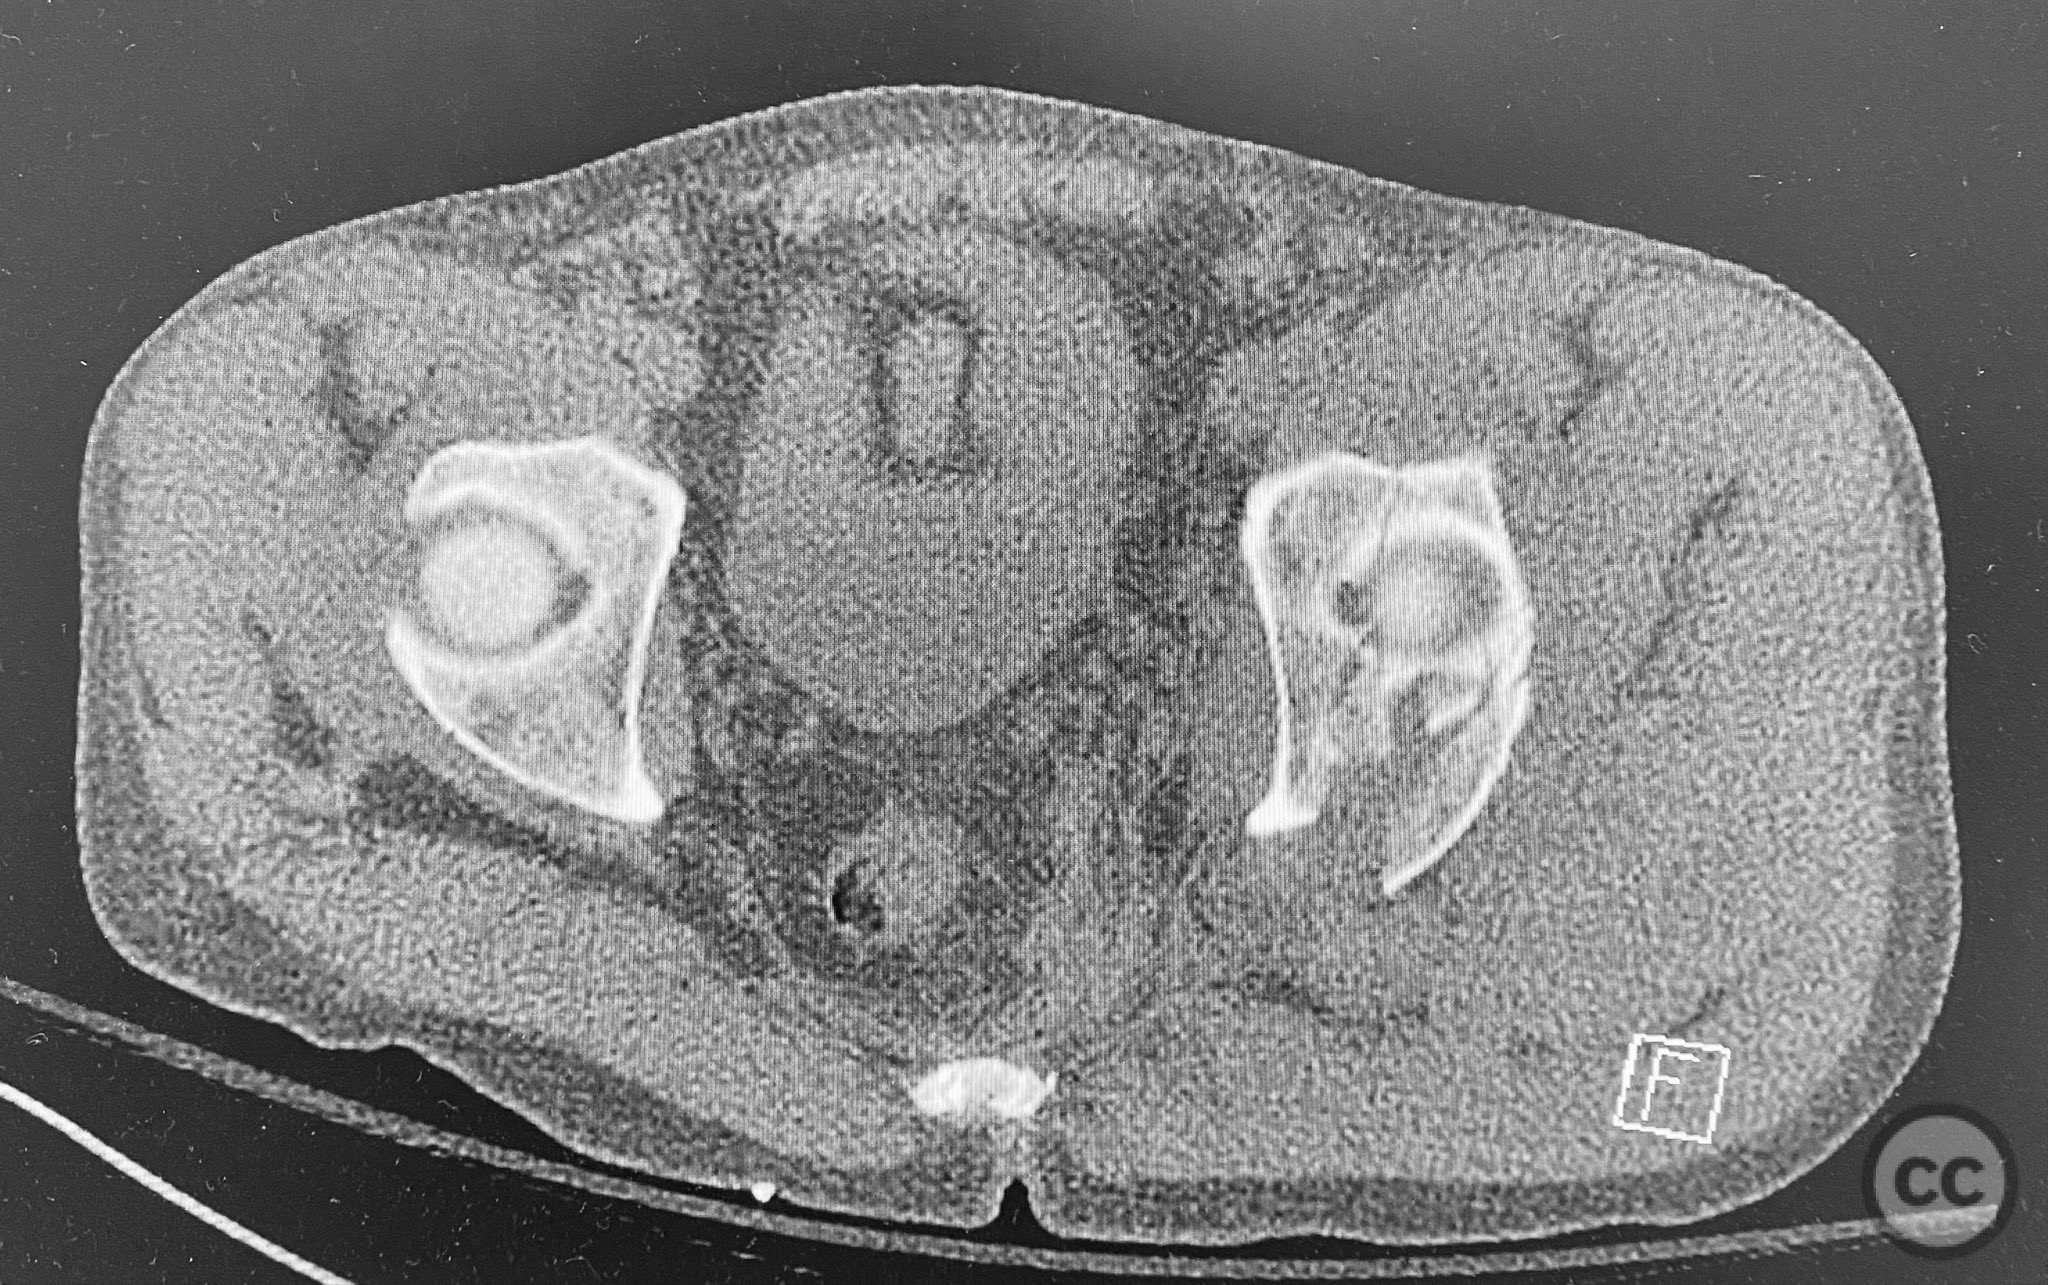

Clinical and radiological findings:  A patient presented with a seemingly non-comminuted, wide, and long posterior wall (PW) acetabular fracture fragment. Axial computed tomography (CT) images demonstrated the thickness of the PW fragment, the articular surface, and multiple areas of subchondral impaction. Preoperative planning identified the size, location, and depth of the impaction zones, as well as an essentially nondisplaced transverse acetabular fracture line, which was not readily apparent on initial imaging. No significant displacement of the transverse component was noted. The AO/OTA classification is 62-B1.3 (posterior wall and transverse acetabular fracture).